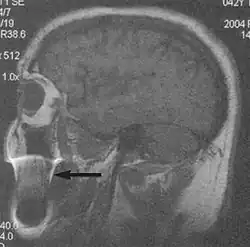

Flow

Flow can manifest as either an altered intravascular signal (flow enhancement or flow-related signal loss), or as flow-related artifacts (ghost images or spatial misregistration). Flow enhancement, also known as inflow effect, is caused by fully magnetised protons entering the imaged slice while the stationary protons have not fully regained their magnetization.[1] The fully magnetized protons yield a high signal in comparison with the rest of the surroundings. High velocity flow causes the protons entering the image to be removed from it by the time the 180-degree pulse is administered. The effect is that these protons do not contribute to the echo and are registered as a signal void or flow-related signal loss (Fig. 2).[1] Spatial misregistration manifests as displacement of an intravascular signal owing to position encoding of a voxel in the phase direction preceding frequency encoding by time TE/2.The intensity of the artifact is dependent on the signal intensity from the vessel, and is less apparent with increased TE.[1]